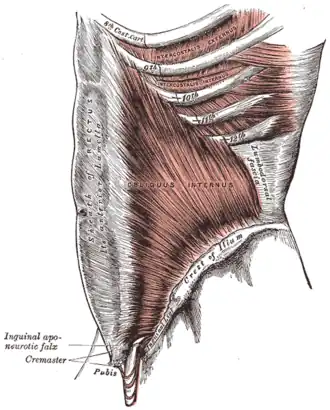

Deep muscles of the chest and front of the arm, with the boundaries of the axilla. (Intercostalis externus labeled at bottom center.)

Deep muscles of the chest and front of the arm, with the boundaries of the axilla. (Intercostalis externus labeled at bottom center.) -